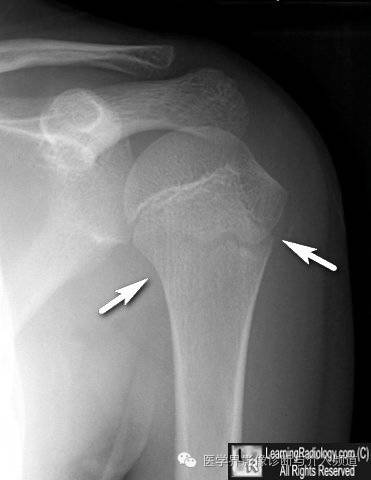

3、肱骨正常骺板:勿误认为骨折线。